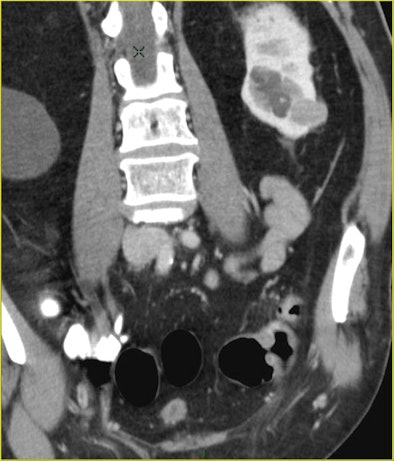

| A 70-year-old man underwent CTC after incomplete colonoscopy at the transverse colon showing a large stenotic lesion in the splenic flexure with bleeding and high-grade dysplasia. CT colonography revealed dolichocolon, a second stenotic lesion in the sigmoid colon, and a tumor in the left kidney, precluding a laparoscopic approach. All images courtesy of Dr. Riccardo Rizzeti. |